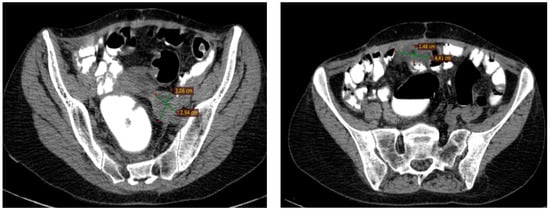

2.2.3. Examinations and Investigations

2.2.4. Diagnosis